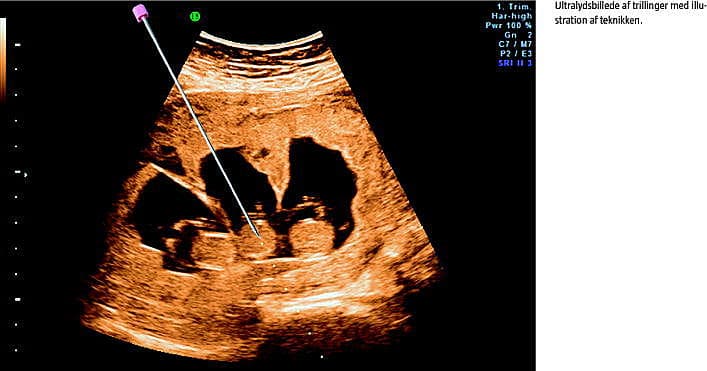

Ved fosterreduktion ombringes et eller flere fostre i et flerfoldsvangerskab selektivt. I Danmark gøres det ved injektion af kaliumklorid intratorakalt eller intrakardielt i fostret. Proceduren udføres transabdominalt og ultralydsvejledt, oftest omkring graviditetsuge 12. Fosterreduktion kan foretages for at mindske de risici for komplikationer, der er forbundet med flerfoldsgraviditeter [1], herunder præmaturitet, abort, dødfødsel, lav fødselsvægt, neonatal mortalitet og morbiditet [2, 3]. Fosterreduktion kan desuden udføres, hvis der konstateres alvorlig sygdom hos det ene foster [4].